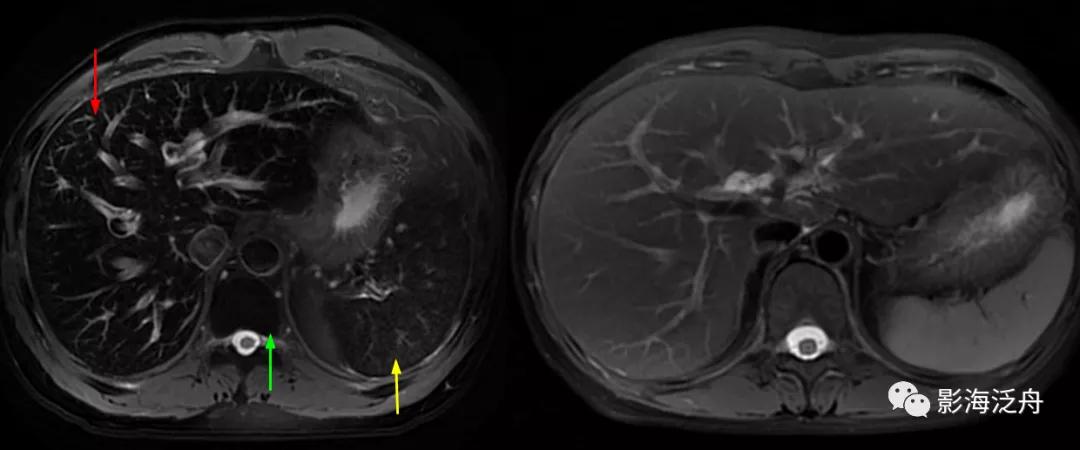

中年女性患者,皮肤黄染、瘙痒一月余前来就诊。能从这幅图像上发现什么问题吗?

将正常人与该患者的T2WI抑脂序列放在一起对比观察。在抑脂较均匀的区域,可以发现该患者肝实质的T2WI信号轻度增高(红箭),门静脉周围的胆管间隙增宽(绿箭),肝周间隙缩小(蓝箭)提示肝脏肿大,脾大(黄箭)。

上图特征不甚明显,需要反复对比观察。